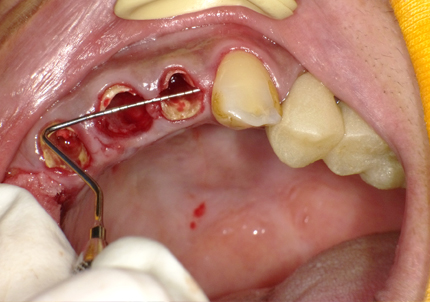

4.右上2番 S.S.T(ソケットシールドテクニック)

5.左上1番 S.S.T(ソケットシールドテクニック)

6.左上2番 S.S.T(ソケットシールドテクニック)

【左下5番ソケットシールドテクニック】

4.左下5番ソケットシールドテクニック